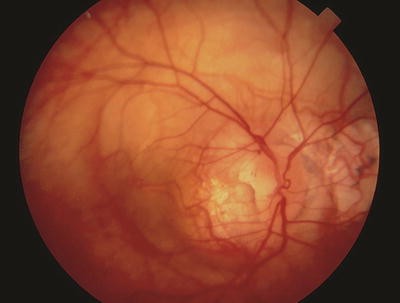

Papillorenal syndrome. The PARSA optic disc is characterized by perturbed angiogenesis, associated renal complications, sans a central retinal artery. Note central excavation with multiple cilioretinal vessels and absence of central retinal vasculature.

Color Doppler imaging has confirmed the absence of central retinal circulation in patients with papillorenal syndrome [286]. Visual acuity is usually 20/20 but may occasionally be severely diminished secondary to choroidal and retinal hypoplasia and, in some cases, to late-onset serous retinal detachments [286]. Peripheral visual field defects corresponding to areas of retinal hypoplasia are often present. The central optic disc excavation and peripheral field defects can simulate coloboma as well as normal-tension glaucoma. Follow-up examination has shown renal disease in some patients who were originally reported as having isolated familial autosomal dominant coloboma [286, 323]. In infants, the bilateral optic disc excavation can simulate congenital glaucoma, but the diagnosis can be established clinically by recognizing the characteristic optic disc morphology [217].